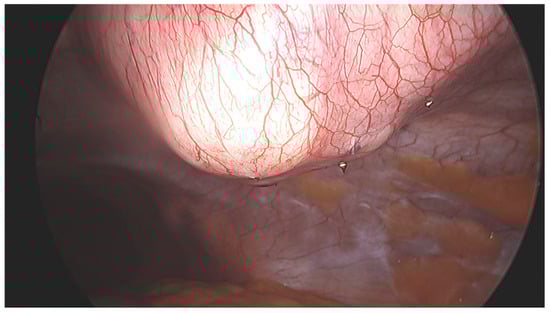

2.2. Procedure and Technique